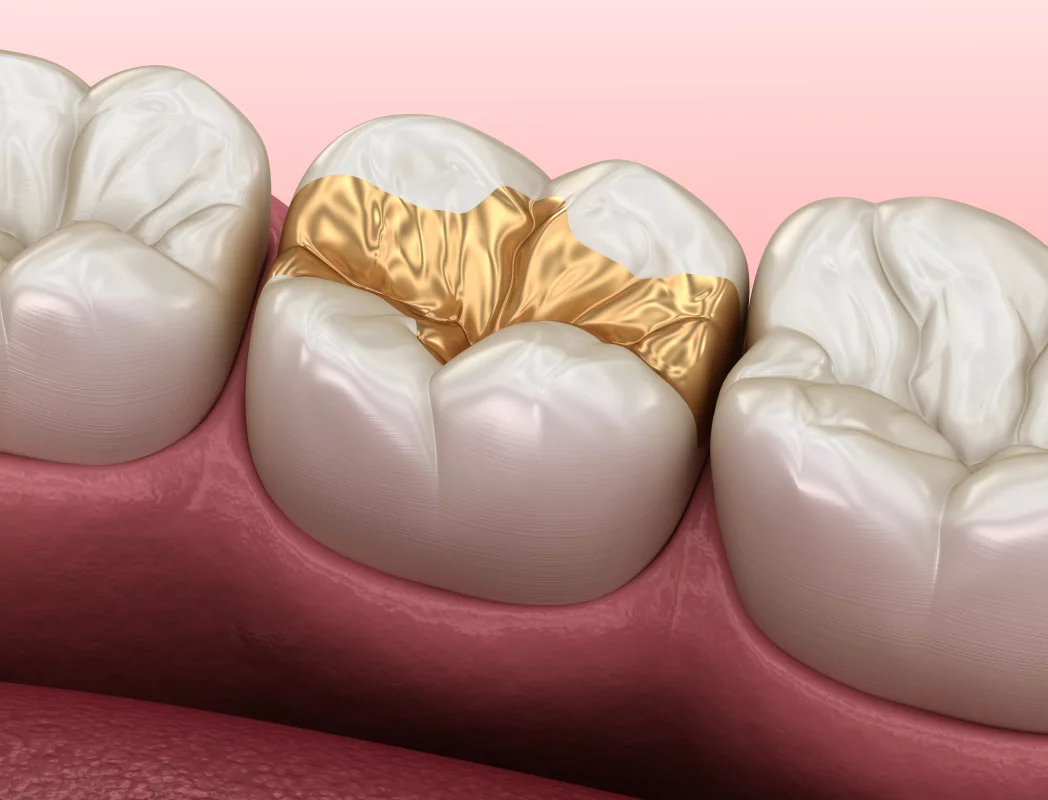

Dabei kann man zwischen verschiedenen Materialien und Füllungsmethoden wählen. Hinzu kommt, dass man als Gesetzlich Versicherter für eine Zahnfüllung in der Regel Zuzahlungen zu leisten hat. Je nach Material und Methode können Zahnfüllungen deshalb sehr kostspielig werden. Nachfolgend geben wir Ihnen einen Überblick zu den gängigsten Füllmaterialien, zeigen die wesentlichen Unterschiede auf und geben Ihnen Informationen, mit welchen Zuzahlungen man als gesetzlich versicherter Patient rechnen muss.